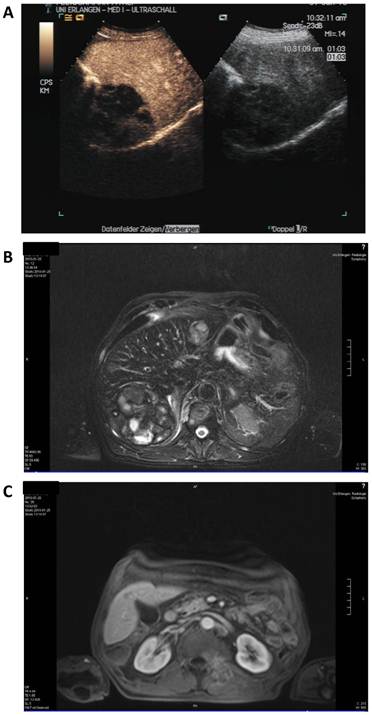

Staging was performed after three cycles in January 2010 (Figure 4). Here, contrast enhanced sonography showed constant lesions in liver segments V, VI and VII (94*80*75 mm) as well as in segment II (29*32 mm) with signs of cirrhosis but no ascites. MRI scanning showed slightly decreasing hemorrhagic lesions with signs of liquid transformation in both liver lobes and of the soft tissue metastasis in the autochthonic spine musculature. No new lesions were discovered. The patient reported diarrhea, exsiccosis, hypocalcaemia and nausea during the last cycle that responded to supportive treatment.

Figure 4

Staging after 8 weeks of sorafenib and panobinostat combination therapy. A: Contrast enhanced (left) and native sonography (right). B: MRI scan of the liver. C: MRI scan of the soft tissue metastasis.